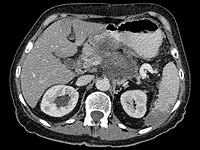

Донор спермы с генной мутацией, радикально повышающей риск развития рака, стал отцом 200 детей по всей Европе. Это выяснилось в ходе масштабного расследования, проведенного крупными вещателями, включая CBS News, BBC News.